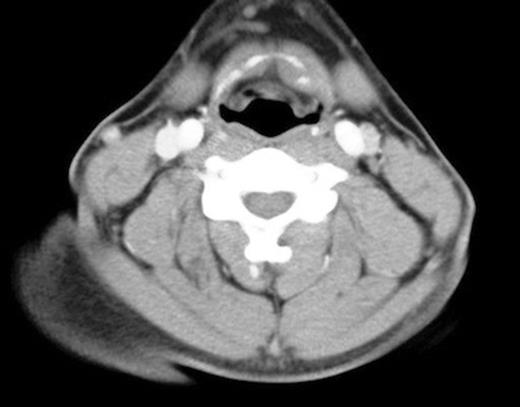

The mechanism of injury and examination findings raised a clinical suspicion of a severe traumatic insult, and he was admitted on the ENT ward to undergo an urgent CT scan of the neck. This demonstrated dislocation of the symphysis between the left medial greater cornu and left body of the hyoid (figure 1).

Dislocation of the symphysis between the left greater cornu and the body of the hyoid bone